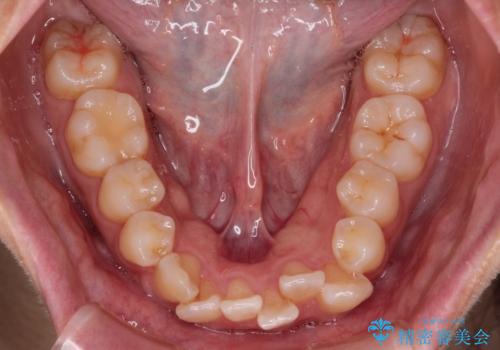

- 上下の出っ歯を気にして来院された患者様です。

口元を積極的に引っ込めるために、上下左右の第一小臼歯を4本抜歯することとしました。